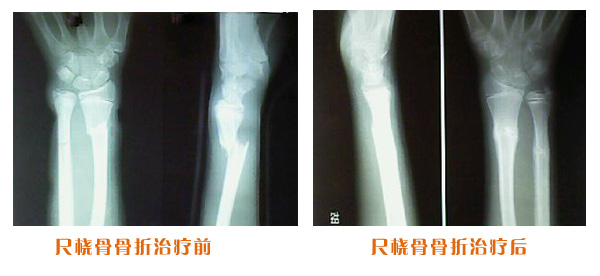

尺橈骨骨折治療前后